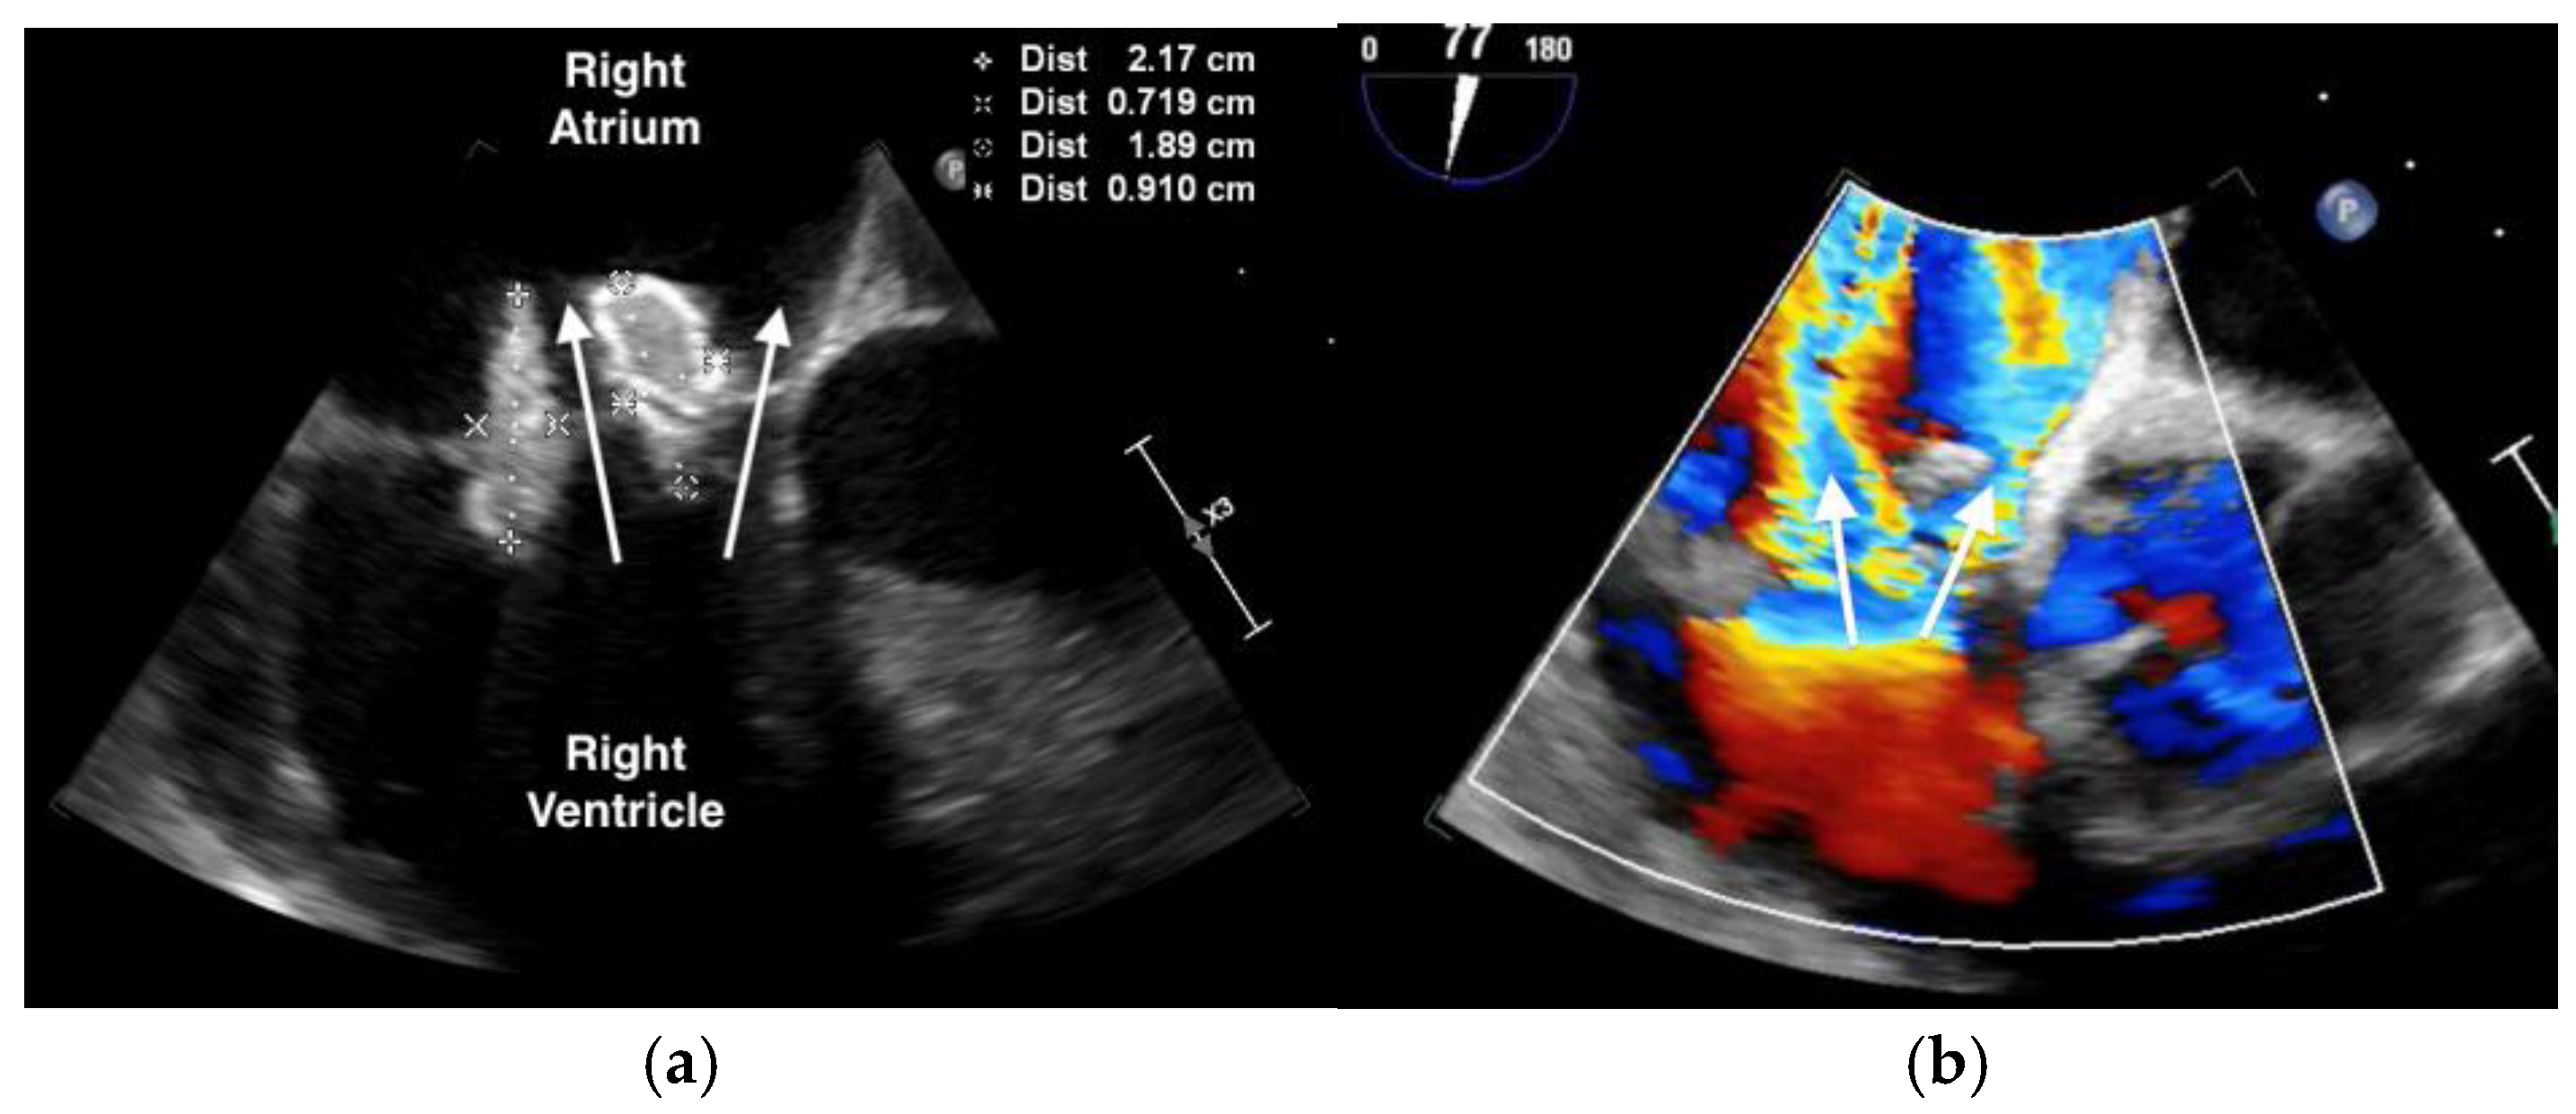

The purpuric rash was clinically consistent with leukocytoclastic vasculitis per dermatologic consultation, although a skin biopsy was not performed. A transthoracic echocardiogram showed normal ejection fraction, but revealed a large tricuspid valve (TV) vegetation (Video S1). A transesophageal echocardiogram confirmed large, multilobed vegetations on the TV measuring 1.9 cm × 0.9 cm on the anterior leaflet and 2.2 cm × 0.7 cm on the posterior leaflet associated with severe tricuspid regurgitation (Figure 2, Videos S2 and S3). (For a video of the transesophageal echocardiogram with cardiologist commentary, see Video S4.)

Figure 2. Transesophageal echocardiogram showing: (a) large, multi-lobed tricuspid valve vegetations associated with valve perforation and (b) severe tricuspid valve regurgitation (white arrow).